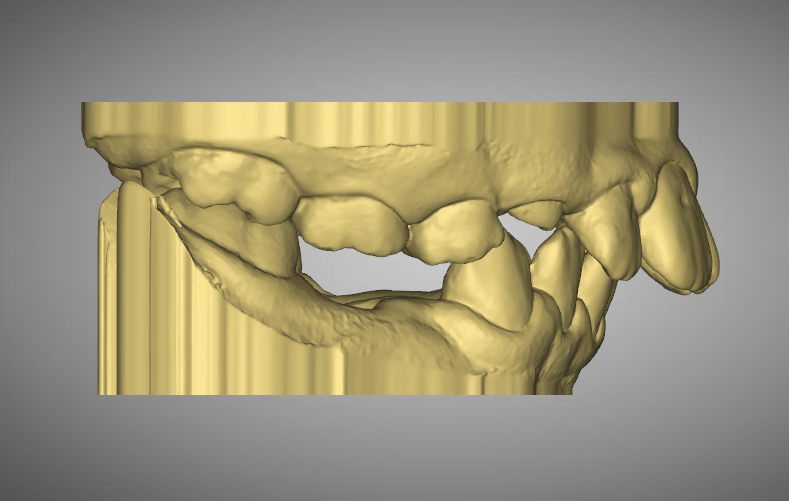

Adaptive Orthodontics Pre-Op Analysis – 2020-11-25 Age : 9 Class 2 div I and div IIMixed DentitionLower lip entrapment NORMALLY LOWER LIP ENTRAPPED BEHIND UPPER ANTERIOR NORMALLY LOWER LIP ENTRAPPED BEHIND UPPER ANTERIOR PROCLINE (OVERJET) UPPER ANTERIORDIASTEMA (SPACING) – TONGUE THRUSTLOWER LIP ENTRAPMENTNARROW (GOTHIC) ARCHDEEP BITE – SOFT TISSUE TRAUMA STAGE 1 RETRACT UPPER ANTERIORS… Read.